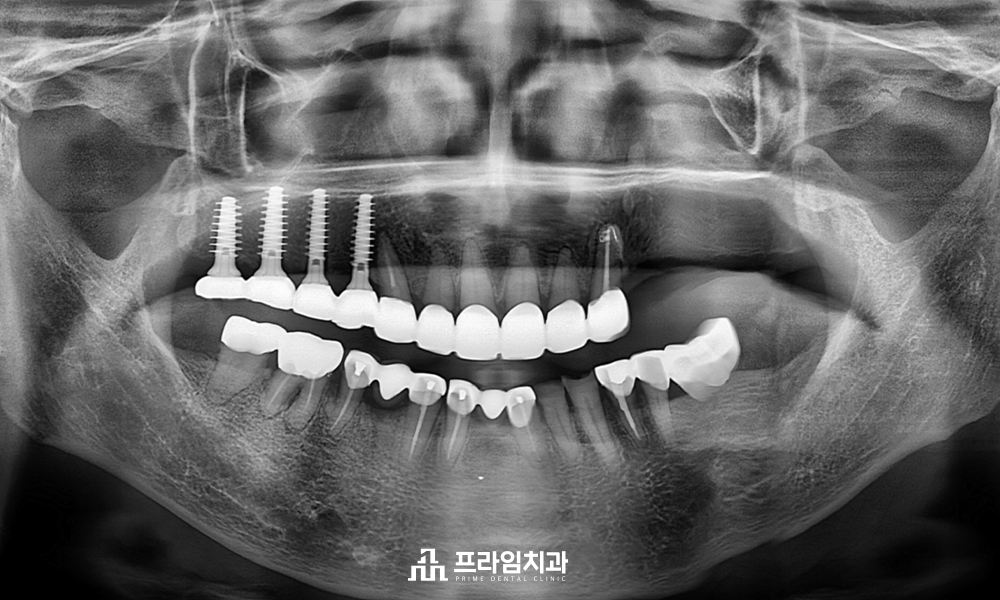

임플란트를 식립 할 때 위아래의

교합을 정교하게 맞추기 위해 아래쪽

보철물을 새로 제작하였으며,

닳아있던 앞니 보철치료까지 완료하여

2년 후 정기 검진을 오셨을 때

촬영한 파노라마 사진입니다.

매직 코어 임플란트의 식립을

통해 빠른 회복과 더불어 환.자분의

꾸준한 관리로 건강하게 유지가

잘 되고 있음을 알 수 있었습니다.

어금니의 임플란트와

앞니 보철치료까지

완료되고 난 후에는 기존 거꾸로

물리고 있었던 교합까지

회복할 수 있었습니다.